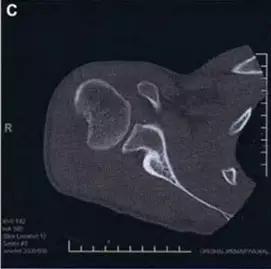

Hill-Sachs 损伤的 CT 片 (来源:Hill-Sachs Injuries of the Shoulder)

- 肩关节前脱位时发生的肱骨头后外侧凹陷性骨折,是经典的 Hill-Sachs 损伤(Hill-Sachs lesion);

- 而肩关节后脱位时发生的肱骨头前内侧凹陷性骨折,是反 Hill-Sachs 损伤(Reverse Hill-Sachs lesion/ McLaughlin lesion)。